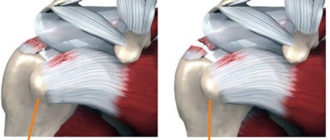

Дегенеративное изменения сухожилия надостной мышцы плеча

Повреждение сухожилия надостной мышцы плеча: лечение частичного разрыва надостной связки, упражнения для надостной мышцы